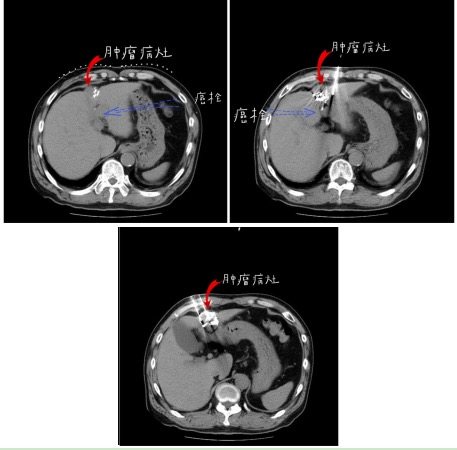

粒子植入术中定位

粒子植入手术术中穿刺

随 后,患者与沈阳市第六人民医院肿瘤介入综合科行肝组织间粒子植入,及门脉癌栓内粒子植入治疗,共植入37颗粒子,术后恢复良好出院。2020年4月8日复 查,肝增强MRI显示,病灶较前缩小,病灶内无明显强化,提示癌灶已坏死,门脉左右及主干支均通畅,肝门部及腹膜后淋巴结较前缩小。AFP 6.74 ng/ml,已降至正常。